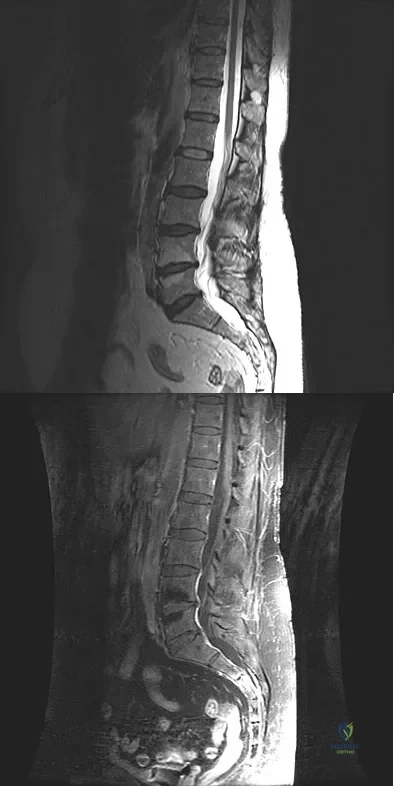

A patient who underwent a L4-L5 hemilaminotomy and partial diskectomy for radiculopathy 8 weeks ago now reports increasing low back pain without neurologic symptoms. A sagittal T2-weighted MRI scan is shown in Figure 13a, and a contrast enhanced T1-weighted MRI scan is shown in Figure 13b. What is the most appropriate management for the patient's symptoms?